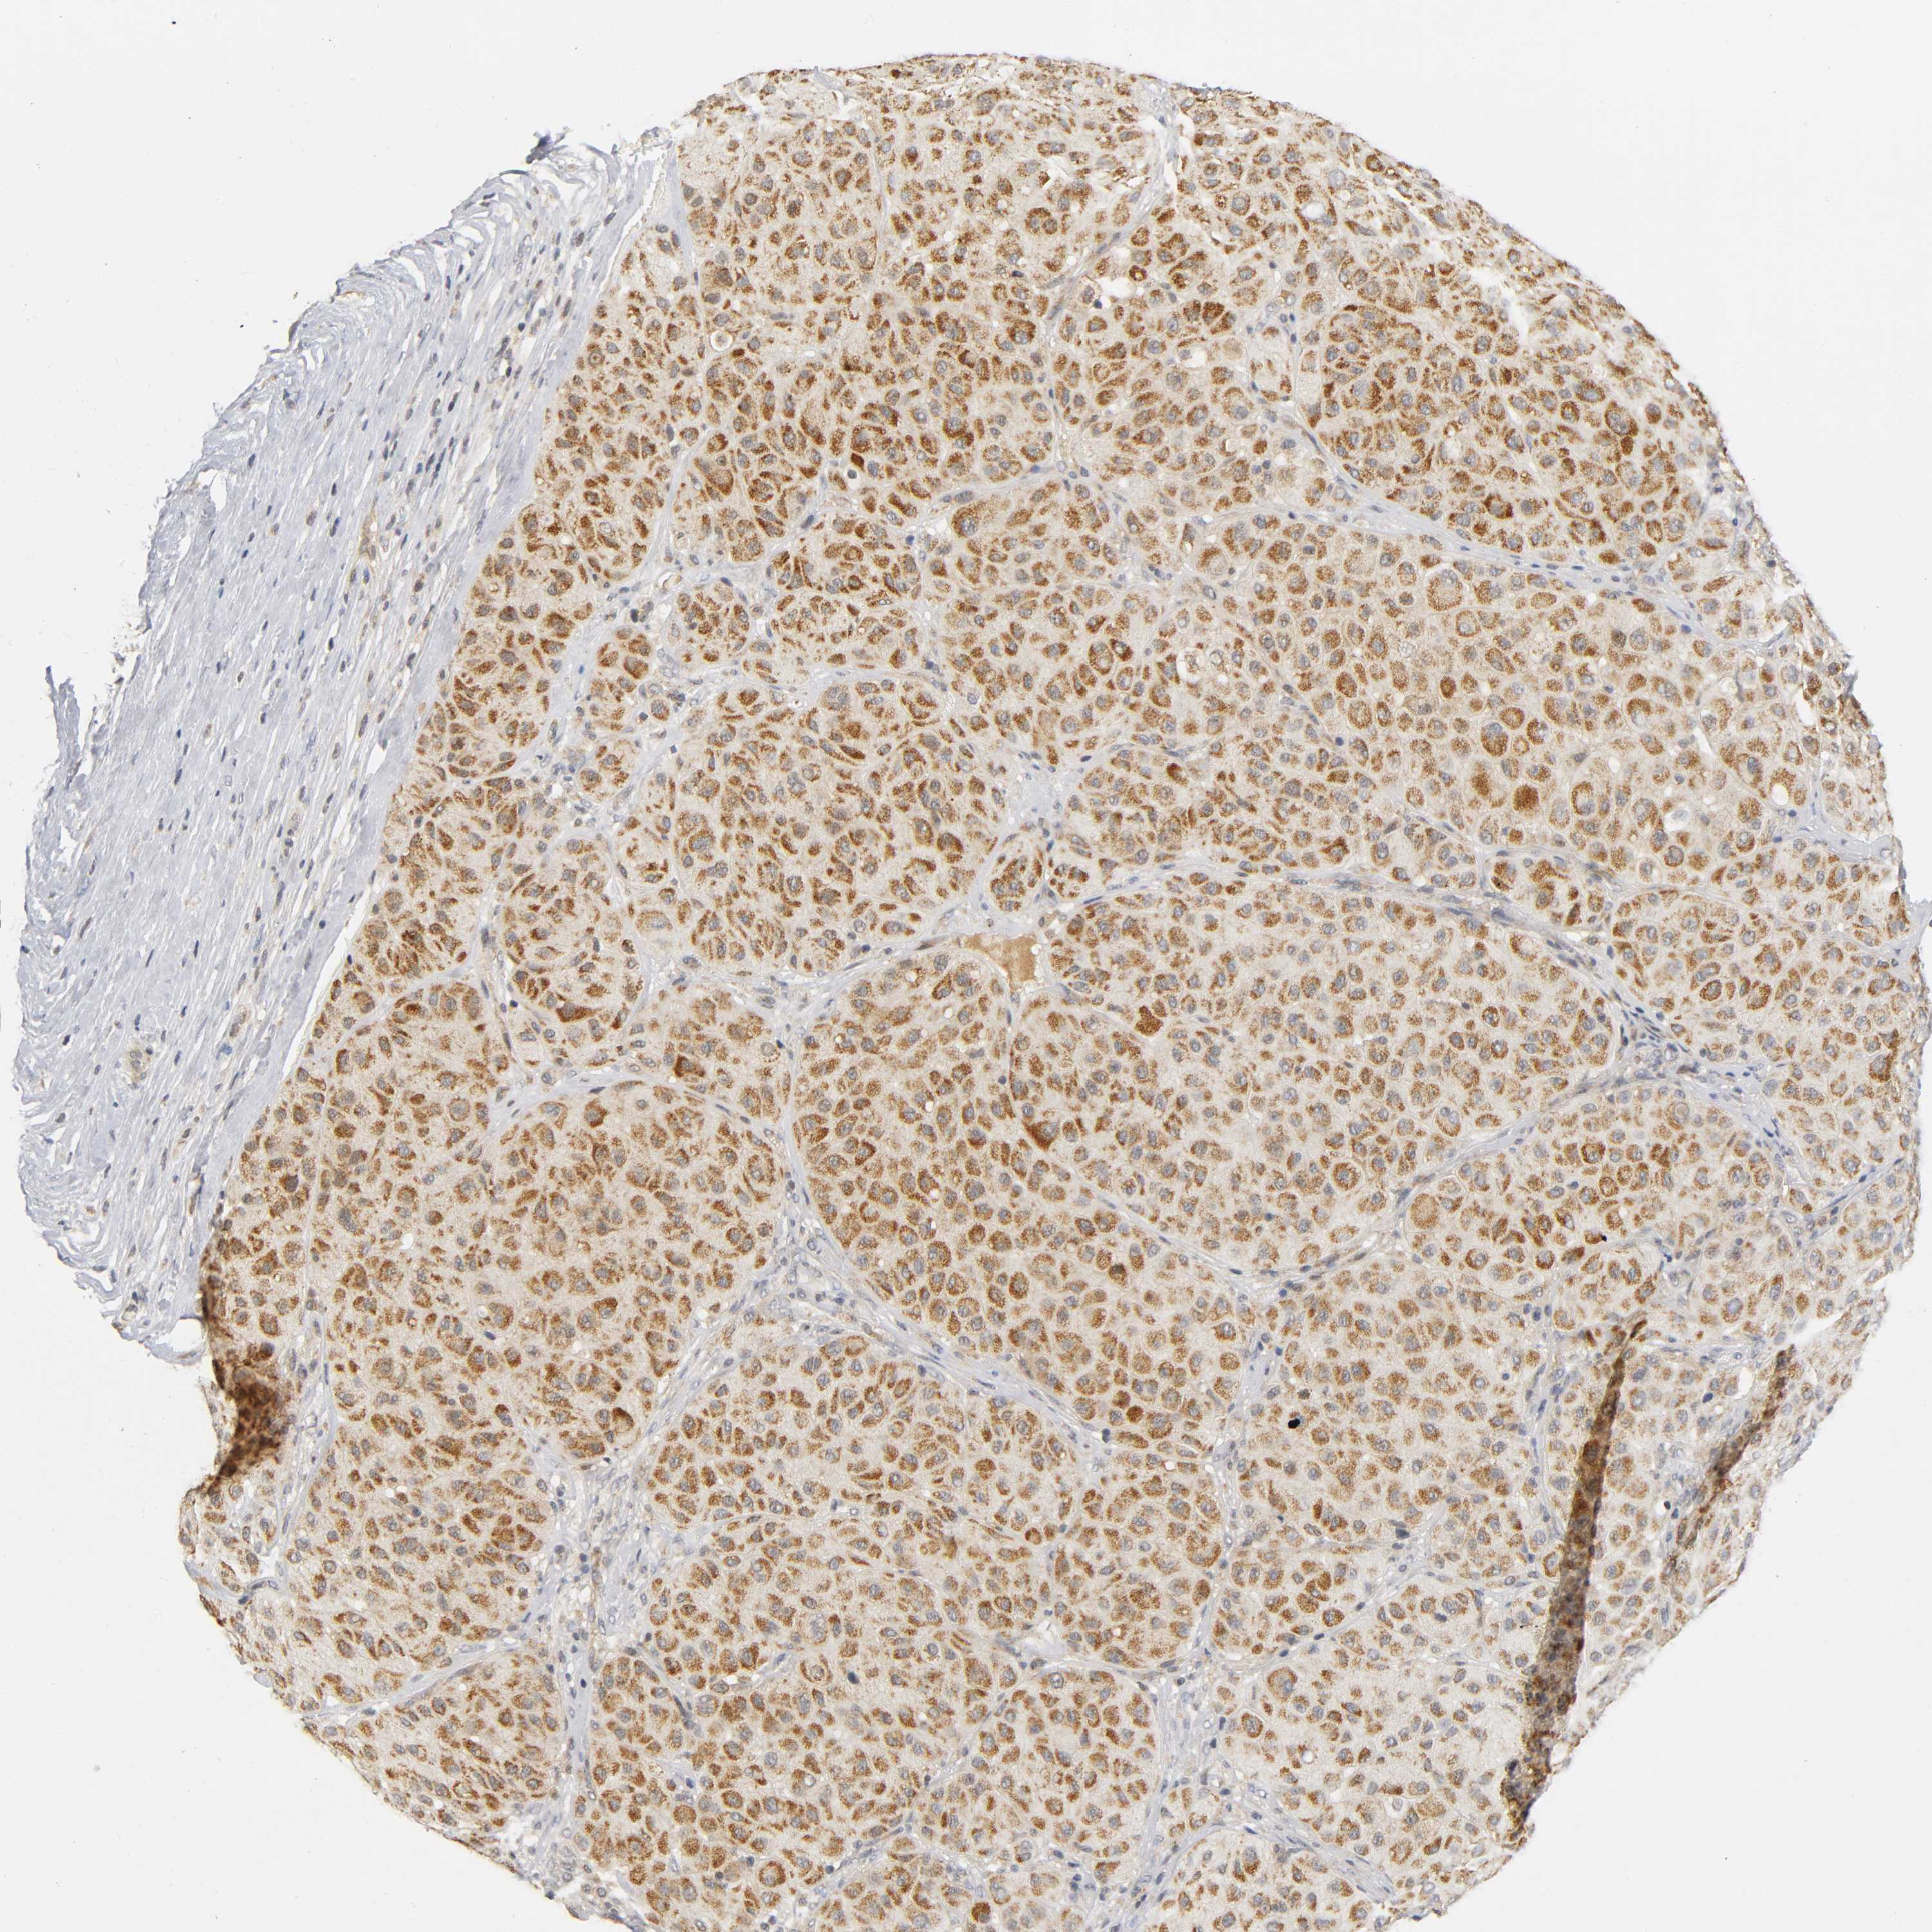

MELANOMA - Protein expressioni

A mouse-over function shows sample information and annotation data. Click on an image to view it in a full screen mode. Samples can be filtered based on level of antibody staining by selecting one or several of the following categories: high, medium, low and not detected. The assay and annotation is described here.

Note that samples used for immunohistochemistry by the Human Protein Atlas do not correspond to samples in the TCGA dataset.

Antibody stainingi

Antibody staining in the annotated cell types in the current human tissue is reported as not detected, low, medium, or high, based on conventional immunohistochemistry profiling in selected tissues. This score is based on the combination of the staining intensity and fraction of stained cells.

Each image is clickable and will lead to virtual microscopy that enables deeper exploration of all samples and also displays staining intensity scores, fraction scores and subcellular localization as well as patient and tissue information for each sample.

Antibody HPA030278

Antibody CAB004511

Staining

High

Medium

Low

Not detected

Intensity

Strong

Moderate

Weak

Negative

Quantity

>75%

75%-25%

<25%

None

Location

Nuclear

Cytoplasmic/membranous

Cytoplasmic/membranous,nuclear

Malignant melanoma, NOS

Malignant melanoma, Metastatic site